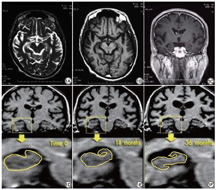

图1为1名75岁男性老年性痴呆患者首诊、18个月后及36个月后海马解剖结构改变的前后对比图,MRI可见患者18个月后及36个月后复诊时海马结构较首诊时显著萎缩。